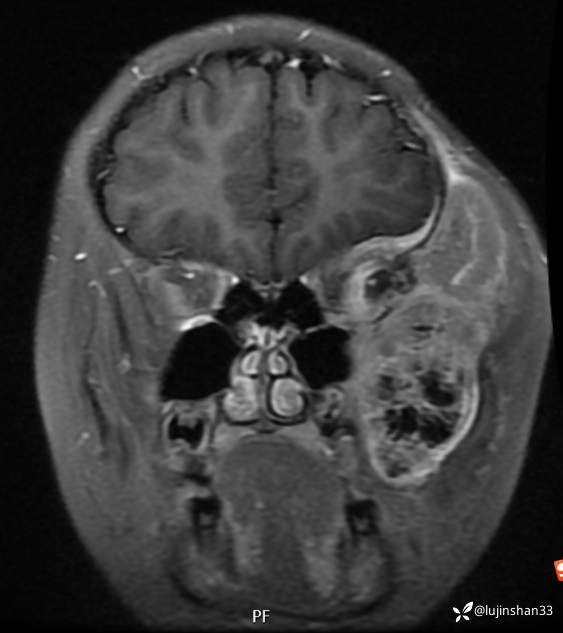

简要病史:患儿父母半年前发现患儿左颞部较右侧突起,无伴随症状,未重视未诊治,1月前,患儿左颞部肿物长大,伴头晕,向一侧倾倒感,头痛,两次剧痛,余为胀痛,偶有夜间出现左下颌区域皮肤麻木,咀嚼时左面部疼痛,10天前,患儿出现左眼睑肿胀伴疼痛,睁眼疼痛加重,不伴视力障碍,无畏寒发热,无意识障碍,无饮水呛咳,在XX同仁医院行颅脑核磁示:左侧颞下窝占位。门诊以“颞下窝占位(左)”收入院。患者目前精神状态良好,体力正常,食欲正常,睡眠正常,体重无明显变化,大便正常,排尿正常。

临床诊断:颅中窝、颞下窝小圆细胞恶性肿瘤

术后MRI:2022年2月考虑复发

2021年8月复查MRI